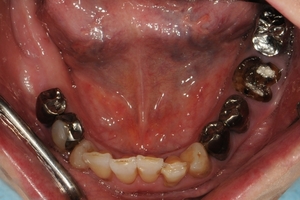

奥歯欠損症例

下顎臼歯2本欠損症例

BEFOREAFTER68歳女性/下2本欠損/インプラント埋込手術 【治療内容】 左下に入っているブリッジか...